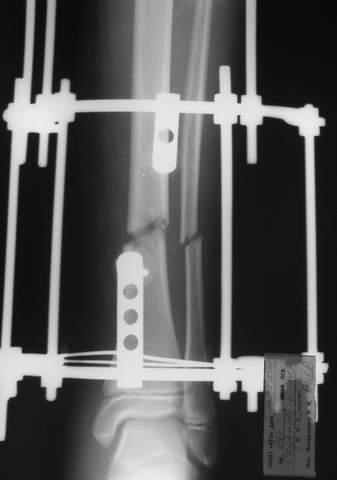

В аттачтах №№ 1 и 2 - примеры, когда 2 кольца не позволили послеоперационно

исправить смещение фрагментов большеберцовой (по ширине и вальгусное).

А казалось бы (#2) - поиграй на штангах и все влетит.

Оперировал не я

1

1a